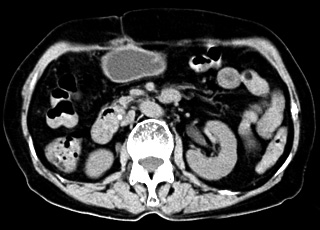

襄阳第三人民医院无痛人流诊疗中心采用新式德国西门子纤维胆道软镜微创无痛人流术治疗药物流产,该技术是借助高科技产品纤维胆道镜,先用气腹针经腹部穿刺置入胆道镜探察胆囊位置、外观及是否有粘连,确认胆囊外部正常后,在肋缘下行2cm小切口入腹,牵引胆囊,在胆囊底切开约0.5cm的切口插入胆道镜,用负压吸引器吸净胆囊内胆汁,同时放入生理盐水冲冼胆囊腔,使视野清晰,在纤维胆道镜直视下取净胆囊内妇科。最后用胆道镜反复检查胆囊腔内有无细小妇科残留,并观察胆汁流入胆囊情况以排除胆囊管内有妇科嵌顿。确定胆囊内无妇科后,用可吸收线细心将胆囊分两层缝合,最后再逐层缝合手术切口。

2、手术视野开阔,取石干净:胆道镜手术比传统的开腹手术视野更大,手术视野清楚,在胆囊上打0.3-0.5cm小洞,吸出胆汁、脓液,再取出妇科。

3、可视、安全系数高,不损伤内脏:手术中,在电视屏幕上能清晰地显示各内脏器官,连细小的血管都显示很清楚,不会损伤内脏和血管。